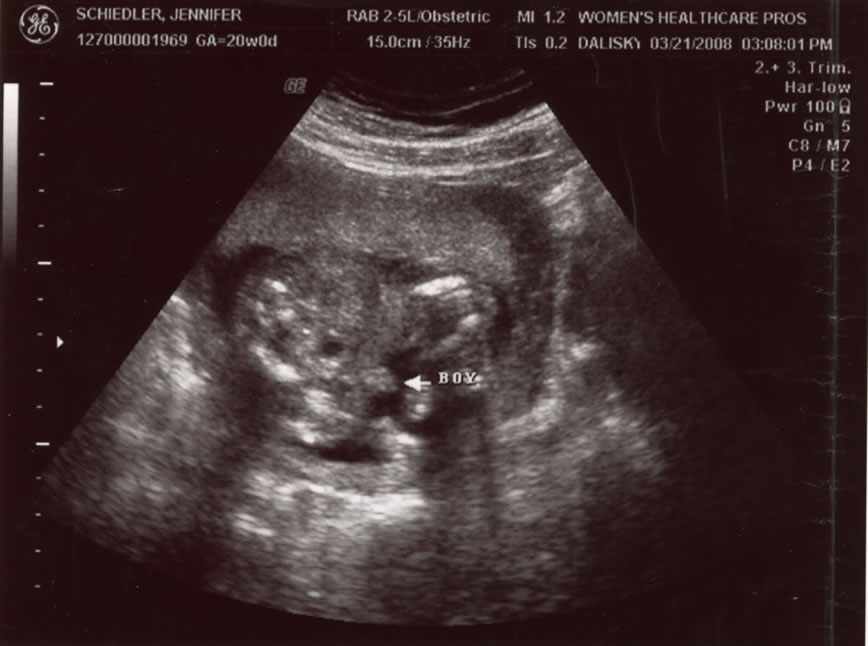

Its a Boy!  3 of 5